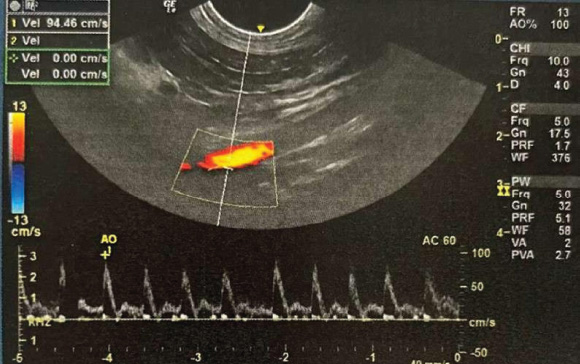

Color Doppler

Color Doppler overlays the B-mode image with color-coded frequency shift mapping. Flows toward the transducer appear in red and opposing flows in blue. The intensity of the colors varies with the flow speed (Thomas et al., 1993; Szatmári, et al., 2001). This technique can quickly assess the presence, direction, and quality of flow in large areas, even when B-mode detection does not identify vessels (Carvalho et al., 2008a).

Semi-parabolic flow (Fig. 8): in intermediate arteries (e.g., celiac artery), with intermediate characteristics between flat and parabolic flow, and a reduced spectral window (Carvalho et al., 2008b; Jenderka and Delorme, 2015).

Fig. 8. Spectral Doppler of the celiac artery, characterized by semiparabolic flow, showing a thin line in systole surrounding a clear space, known as the spectral window. Source: Personal archive, 2025.

The best image of the celiac artery is obtained with the patient in the right dorsal or lateral decubitus position, close to the right kidney (Carvalho et al., 2008a). The transducer is positioned ventrally to the lumbar processes and tilted dorsally to locate the aorta. With the aorta in a longitudinal plane, the transducer is moved cranially until the celiac artery and the cranial mesenteric artery are identified above the origin of the renal arteries. The celiac artery has a semiparabolic flow velocity profile and an intermediate resistance pattern. A broad systolic peak is observed with a well-defined mean spectral window and absence of reverse diastolic flow (Szatmári et al., 2001; Carvalho et al., 2008a).

Located below the celiac artery and above the right renal artery, the cranial mesenteric artery forms a “V” in the sagittal plane with the celiac artery when the patient is in the supine position. In the right lateral decubitus position, both directions follow parallel paths until they approach this point (Carvalho et al., 2008a). In spectral Doppler mapping, the cranial mesenteric artery shows a flow pattern of intermediate resistance with a broad systolic peak and small spectral window. After the systolic peak, the flow velocity decreases abruptly, accelerates, and then decelerates again. During fasting, the flow is of high resistance and of low resistance in the postprandial period due to increased blood flow to the stomach, duodenum, and pancreas after food intake (Carvalho et al., 2008b).